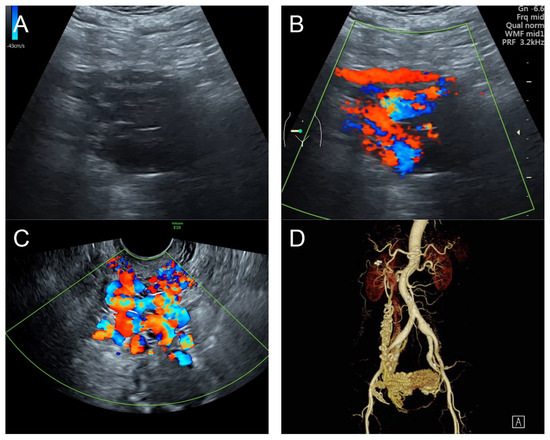

(A,B) Transvaginal ultrasound: sagittal scans of the uterus showed several small anechoic/hypoechoic cysts, giving a spongy pattern and varying in size, throughout the myometrium; no other specific lesions of the uterus. The uterine cavity was lined with a thin endometrium and filled with anechoic fluid, probably lysed blood. (C) Color flow mapping showed hyper-vascularization in the cystic spaces, as seen in figure (A,B), throughout the myometrium and a multidirectional chaotic flow. The main differential diagnosis was adenomyosis or gestational trophoblastic disease. (D) Spectral Doppler showed a high peak systolic velocity (~70 cm/s) with a low resistance index of 0.2.

Management: Initial therapy included fluid resuscitation, blood transfusion, trans-rectal misoprostol at 800 mg, and intrauterine tamponade with a Foley catheter balloon, resulting in a reduction in bleeding, but significant bleeding still persisted. A transabdominal total hysterectomy was successfully performed, with satisfactory outcomes. The operative findings and pathological examination confirmed the diagnosis of uterine AVM. The patient was healthy and asymptomatic at the 6-week post-operative check-up. However, unfortunately, she was lost to follow-up after this point.